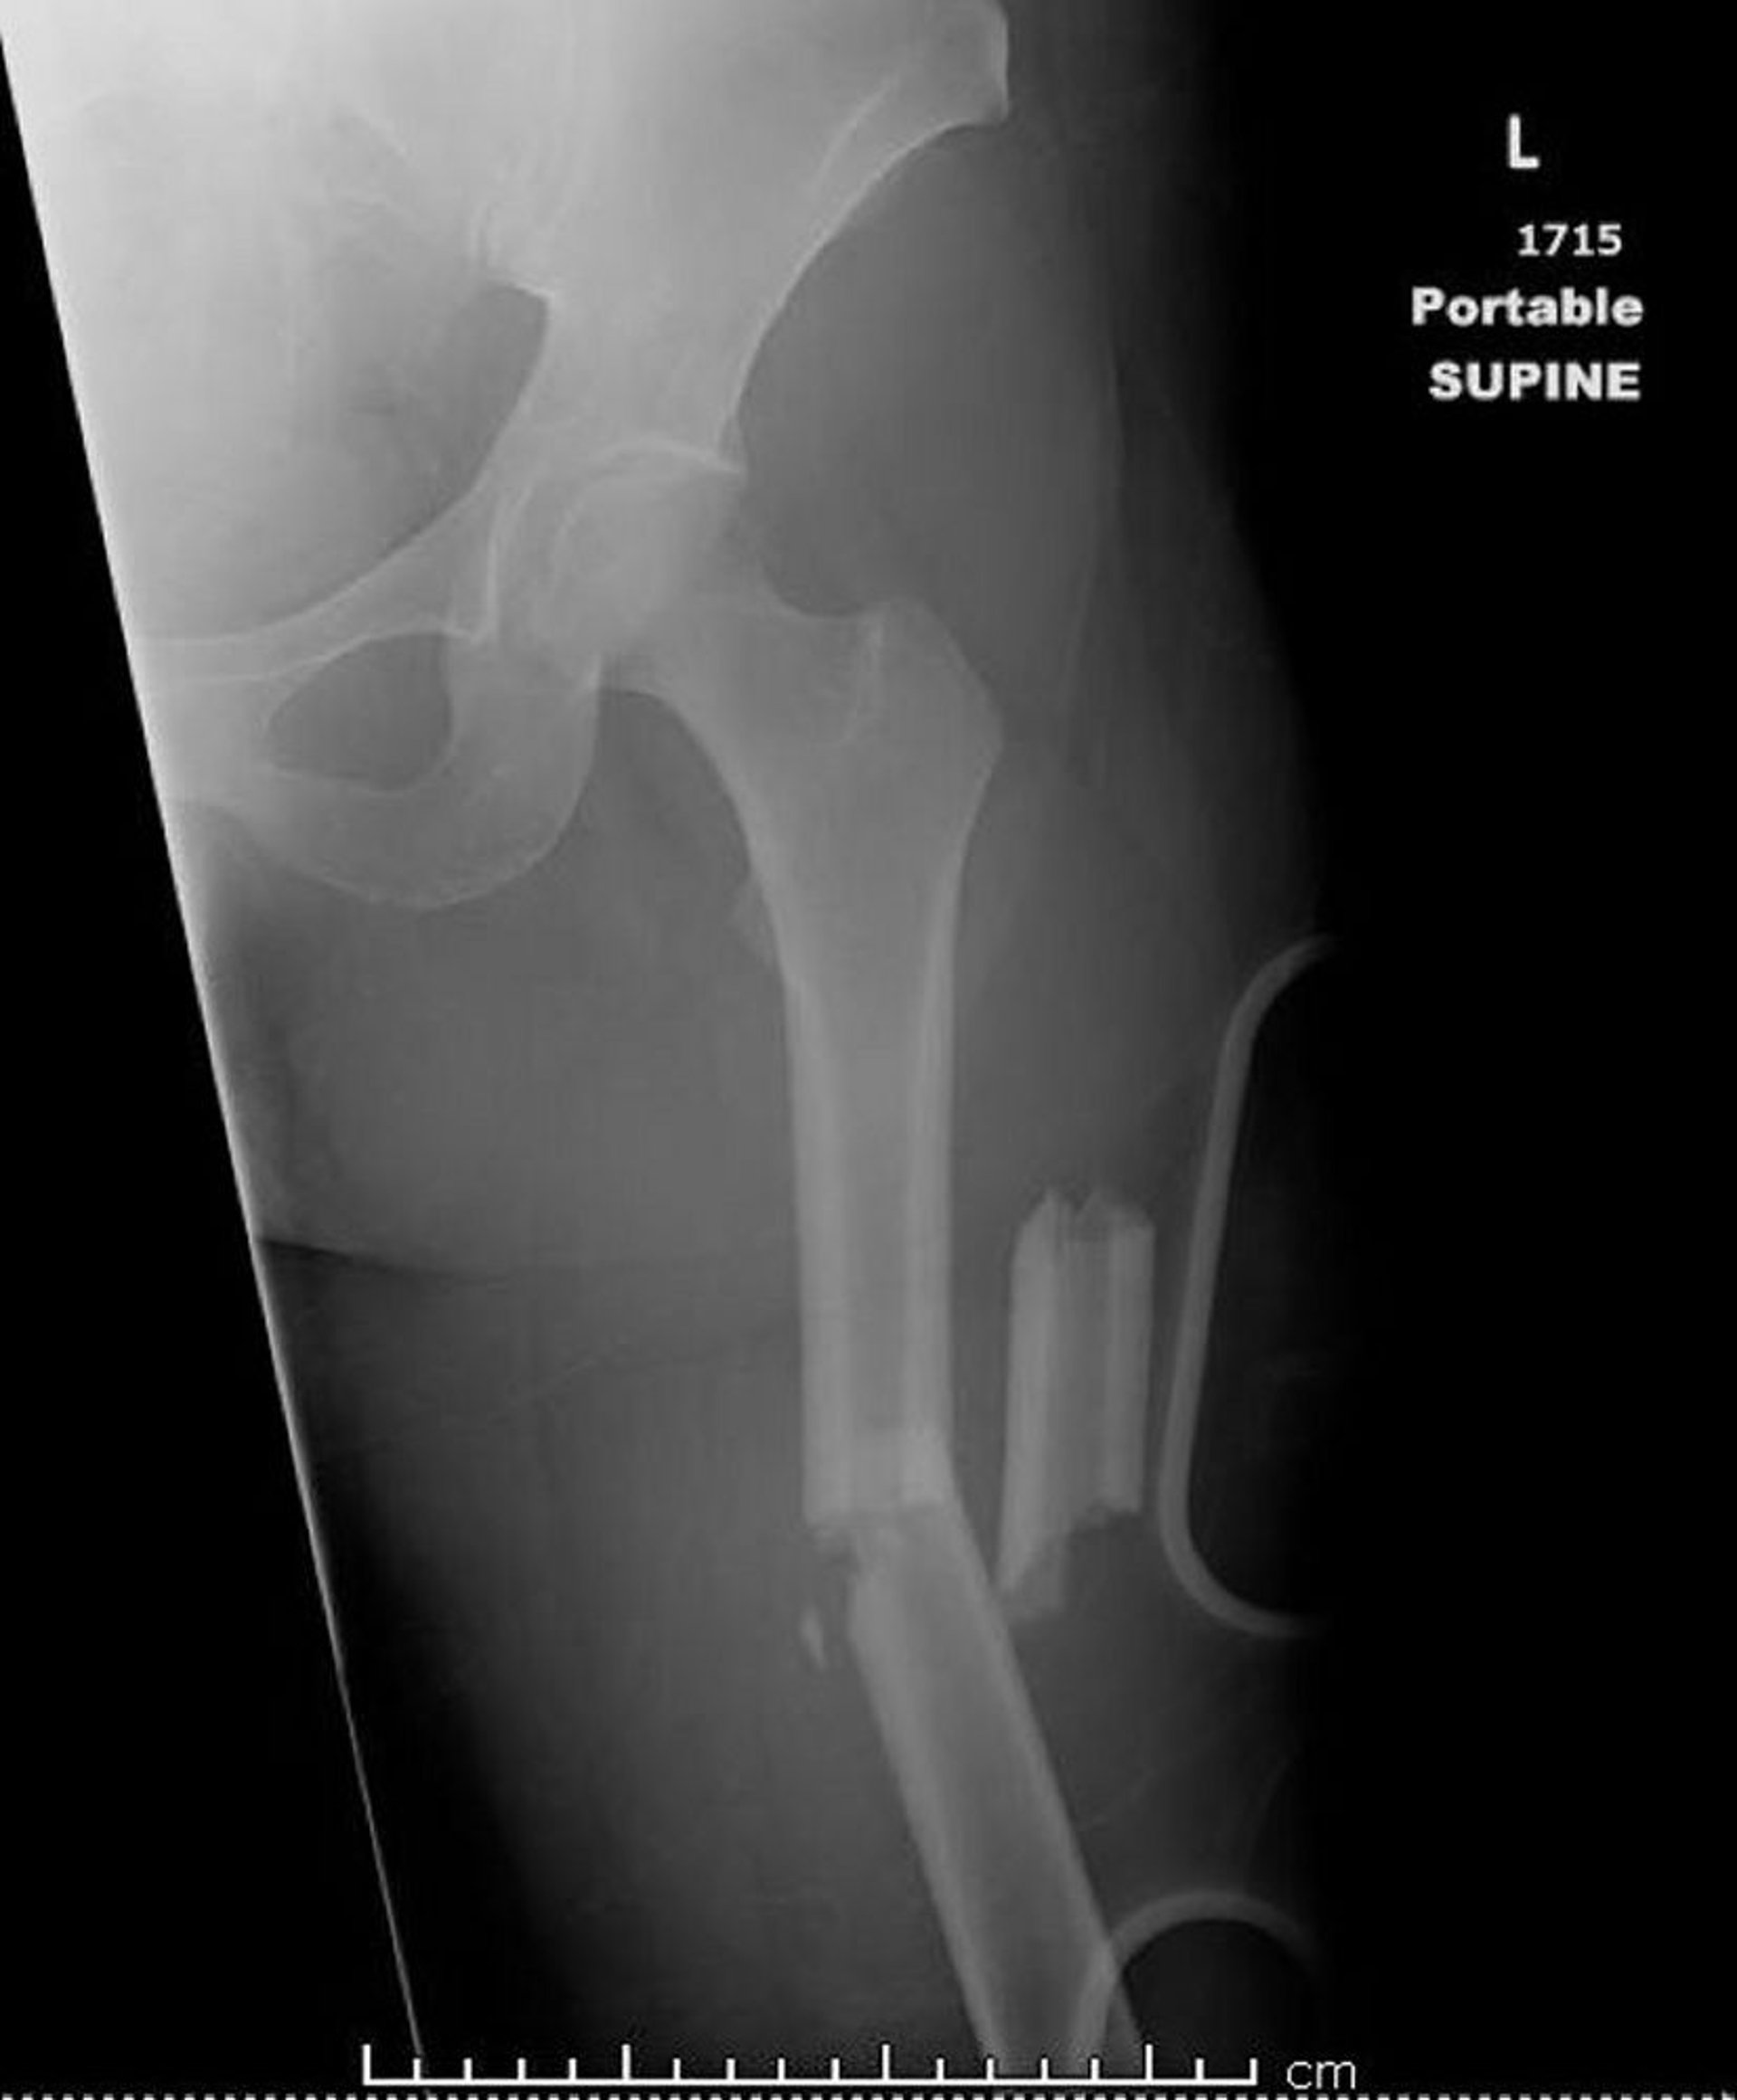

Frattura mediale della diafisi femorale (1)

Questa immagine mostra una frattura comminuta, angolata e accorciata mediale della diafisi femorale.